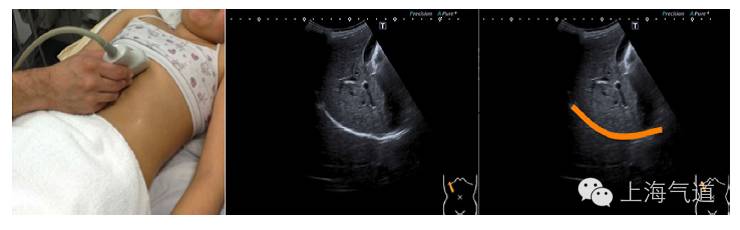

图8探头置于肋下,右半横膈超声影像为高亮回声线(标记为橙色),吸气时会迎向探头方向移动。左半横膈因为心脏的位置而较难定位